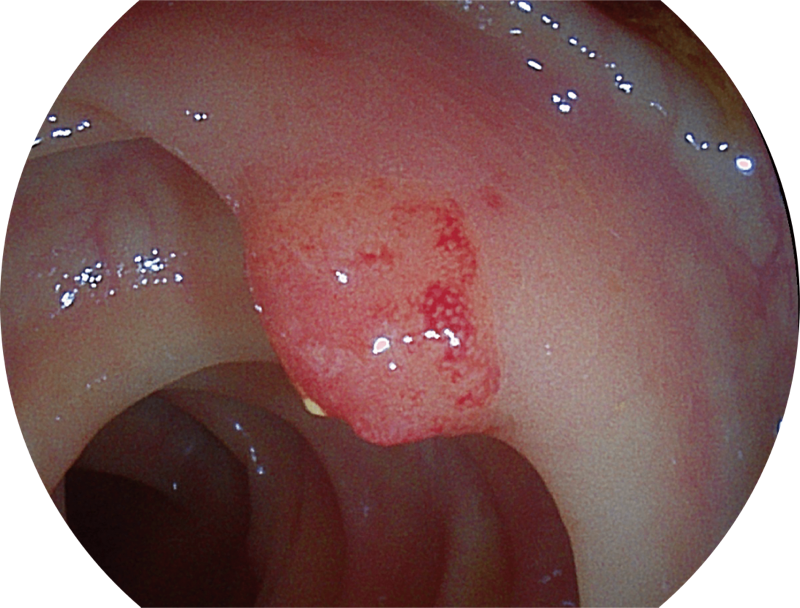

(Spectral Focused lmaging, SFI)

能够凸显黏膜浅层和中层血管轮廓,适用于中、远景观察下的病灶识别和早癌筛查。

(Versatile Intelligent Staining Technology)

能够凸显黏膜浅层血管轮廓和黏膜表面微结构,适用于中、近景观察下的早癌精确诊断。